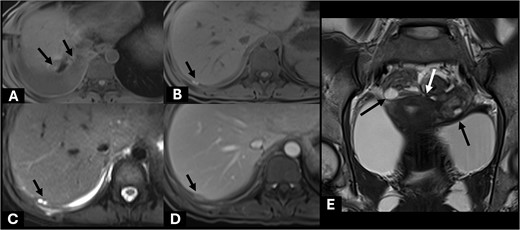

The patient was admitted for intravenous hydration, antibiotics, and close monitoring. Magnetic resonance cholangiopancreatography (MRCP) confirmed a normal appearance of biliary system without bile leakage or fistula. However, few subperitoneal nodules compatible with endometriotic implant nodules were noted (Fig. 4). No major biliary leakage was identified byendoscopic retrograde cholangiopancreatography (ERCP), however, a plastic stent was placed to decompress biliary tract. Further history taking revealed progressive dysmenorrhea over the past year, which was much worsening by expanding from suprapubic area to entire abdomen.

Axial precontrast T1W images (A, B) showed few subhepatic nodules (short black arrow) demonstrating hyperintensity, which measured up to 15 mm abutting posterior right hepatic capsule. It showed hyperintensity on T2W (C) and homogeneous enhancement on post contrast enhanced MRI (D). These findings are suggestive of endometriotic implant nodules with subacute hemorrhagic foci (short black arrow). Included MR pelvis on coronal T2W image (E) showed complex cystic lesions at both adnexae (long black arrow) with adjacent fibrosis (white arrow) creating kissing ovary sign appearance. These findings are compatible with pelvic DIE.